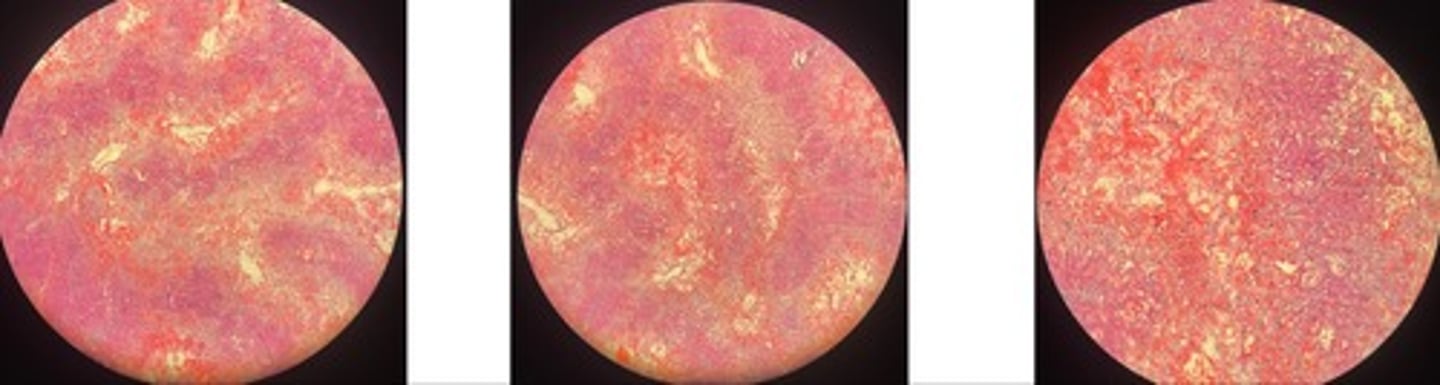

Contagious Bovine Pleuropneumonia (CBPP)

- fibrous pneumonia = acute, red, grey (increase neutrophils), resolution

- area of necrosis w/ bv @ centre + inflam cells surrounding

- marginal organisation…. granulation grows to surviving lobes

Equine Infectious Anemia (EIA)

- necrosis of central lobes

- congestion of c.v + sinuses

- hemosiderin + inflam cells in triad

- hyperplasia of Browicz-Kupfur cells

Infectious Canine Hepatitis (ICH)

- hepatic necrosis

- congestion + inflam infiltrate

- intranuclear viral inclusion bodies (basophilic)